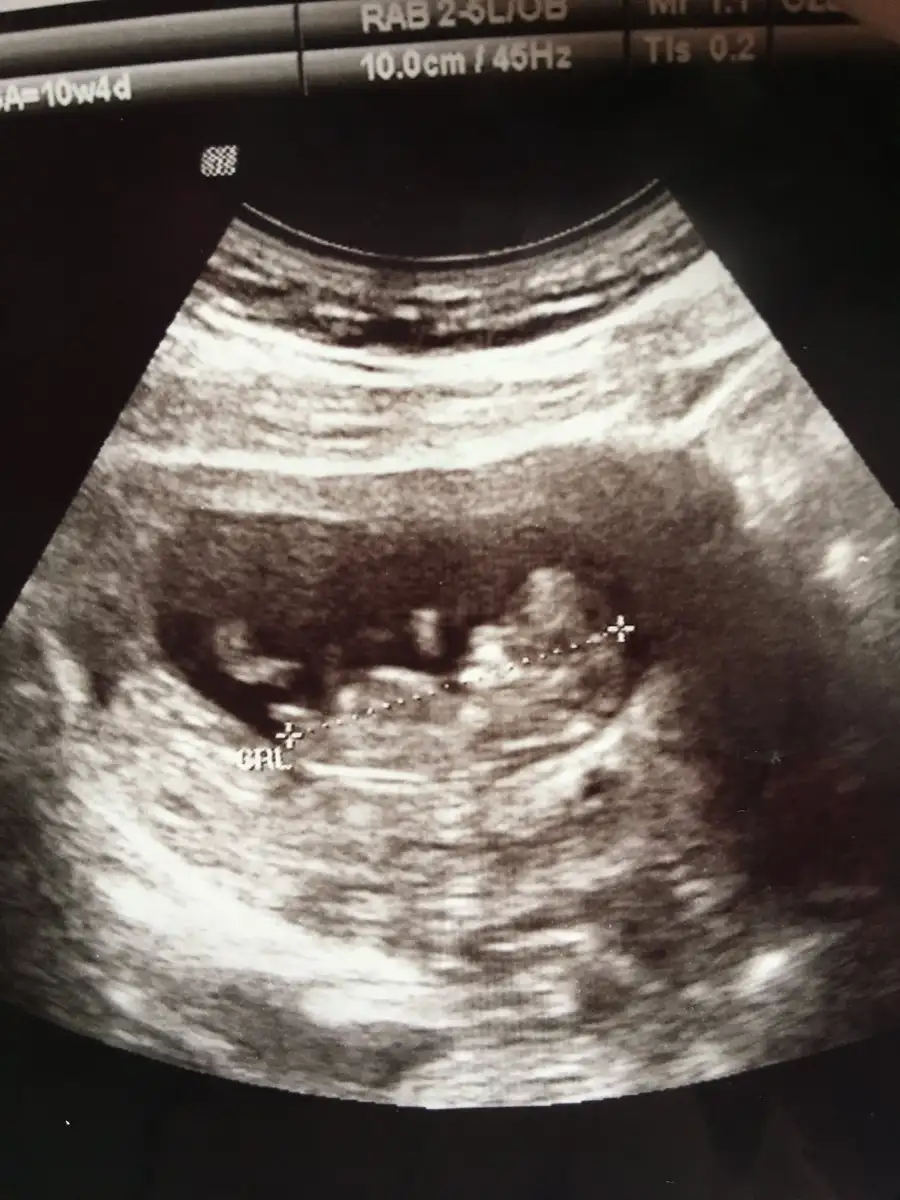

Korkma canım benim korkutmak için söylemedimmm. Bazı bebişler başlarda ilerde bazıları sonradan öyle bir gelişiyor kiYok geç döllenme felan değil. Tam zamanında ilerliyor. Şuanda ne ileri ne geri. 13+2 deyiz. Yani 14. Hafta içerisinde. Doktorum da herşeyin normal ve yolunda olduğunu söyledi. Ense kalınlığımız 1,0 çıktı.

Devlette 16. haftadan önce cinsiyet nedeniyle kürtajın önüne geçilmesi için söylenmiyor demişlerdi buradaki arkadaşlar ama bilemiyorum ben hiç gitmedim devlete. Ama ultrason fotosu ile burda tahmin yapabilen arkadaşlar var. Buraya eklersen sana da tahminler gelecektir :)Canim geçmiş olsun inşallah en kısa sürede geçer. Merak etme 1 kaç haftaya tik diye keser . Ben 7 gündür çok iyiyim tak diye kesildi decavit vitamine başladım ondan mi nedir bilmiyorum bazen diğer kızlar gibi Ben dr korkuyorum belirti yok acaba iyimi diye :)

Bakalim inşallah söylerler. Resim eklemeyi isterim ama verdikleri resim karaltı gibi hiç bir şey anlaşılmıyor:)) söylemezler se 2 hafta sonra özel e gideceğim o zaman öğrenirim insallahDevlette 16. haftadan önce cinsiyet nedeniyle kürtajın önüne geçilmesi için söylenmiyor demişlerdi buradaki arkadaşlar ama bilemiyorum ben hiç gitmedim devlete. Ama ultrason fotosu ile burda tahmin yapabilen arkadaşlar var. Buraya eklersen sana da tahminler gelecektir :)